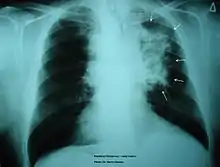

The morbidity of cigarette smoking is nearly 50% with 7 million first-hand smokers and 1.2 millions second hand smokers killed each year[8]. Regardless of active or passive smokers, macrophage accumulation is found in the lungs.[3][5] The diagnostic methods for smoke-related diseases include bronchoalveolar lavage which can also be used for examining smoker's macrophages in addition to augmented inflammatory cells in the alveolar lumen.[1]

The immune functions in smoker’s macrophages are compromised, so the airway pathogens are more likely to accumulate and cause infection.[17] Smoker’s macrophages have reduced expression of HLA-DR antigens, causing immunosuppression.[18][19] In addition, nicotine impairs the phagocytosis of M. tuberculosis and also induces immunosuppression via the activation of alpha-7 nicotinic receptors.[4][17] Meanwhile, due to the impaired TLR2 and TLR4 signaling, macrophages fail to recognize pathogens, so there is a decrease in pathogen clearance.[17] Therefore, smokers are prone to acute respiratory tract infection and community acquired pneumonia.[20]